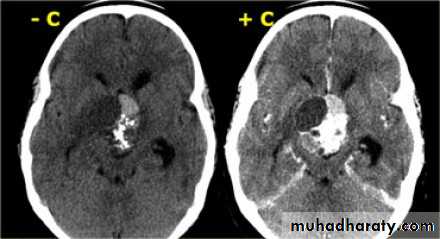

Glioma

Comments primary interracial tumor , vary greatly in malignancy , have many names depending on the histological type :

gliobtastoma multiforme G IV highly malignant t. named also as butterfly G. arise from the anterior or posterior aspect of the corpus callosum , extend & spread to both cerebral hemispheric sides

IV( glioblastoma multiforme ) are highly malignant have all previous mentioned features .

CT Scane